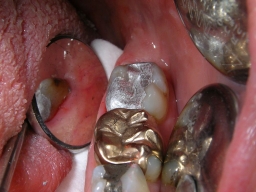

Schmerzhafter Haarriß, mit Amalgam beschwerdefrei

Gleicher Zahn (37). Zuverlässige Therapie einer schmerzhaften Infraktur, d. h. eines unvollständigen Zahnbruches, mit Amalgam, die mit Composite vermutlich nicht funktioniert hätte.

Frisch gelegte u. brünierte Amalgamfüllung